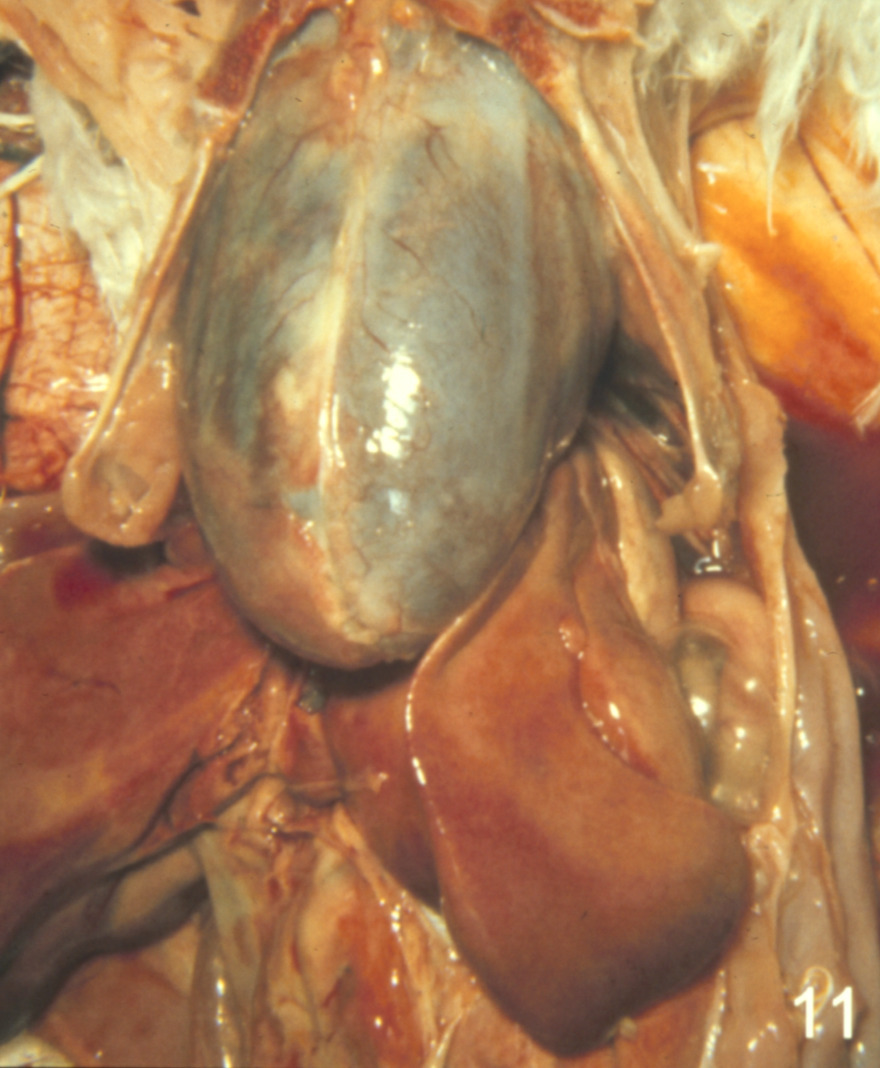

Cardiovascular disease in turkeys (slide study set no. 24)

Turkeys--Diseases Cardiovascular system--Diseases

Slide Study Set #24, Cardiovascular Diseases in Turkeys (includes 27 color slides), 2001